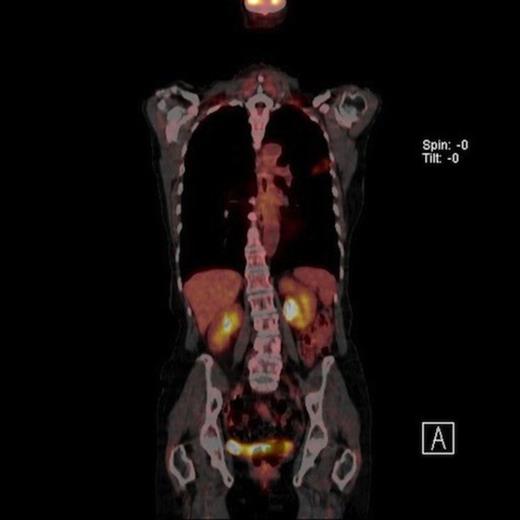

A 61-year-old female smoker (42 pack years) was found to have left upper zone shadowing on chest X ray following a history of weight loss. Her performance status was 1 with a Forced expiratory volume in one second (FEV1) of 1.94 Litres. Positron emission tomography in conjunction with computed tomography (PET-CT) showed two nodules in the left upper lobe. There was a 2cm spiculated lesion in the anterior segment with a Standardised Uptake Value (SUV) max of 5.6 units (Fig 1A) and a 2.2 cm cavitating lesion in the apico-posterior segment with a SUV max of 2.7 units (Fig 1B). There was no radiologic evidence of mediastinal lymhadenopathy or distant metastases.

Coronal view of PET CT scan of moderate uptake synchronous nodule in the left upper lobe